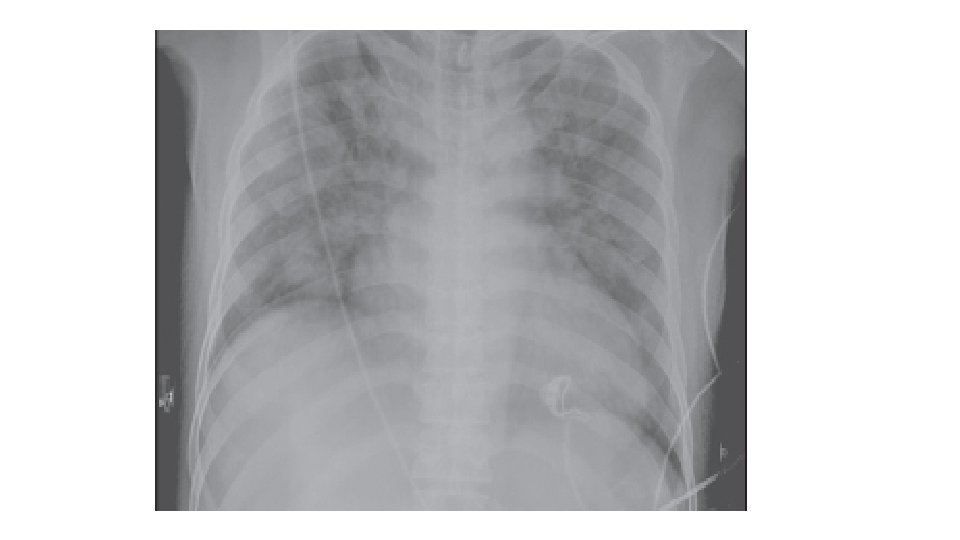

TACO SIGNOS Y SINTOMAS: Taquicardia, disnea, taquicardia, aumento de presion arterial sistólica y diastólica, pulsos saltones, estertores, saturación baja Radiografia : Cardiomegalia e infiltrados bilaterales , Lineas de Kerley , redistribución vascular hacia los apices, derrame pulmonar bilateral. PVC, PAP en cuña elevadas, Saturación bajas. Peptido natruretico cerebral Aumentado. 9

Criterios de reporte para TACO Deben de tener compromiso respiratorio agudo o que empeora durante o hasta 12 horas después de la transfusión y deben de mostrar dos o más de los siguientes criterios: Ø Evidencia de edema pulmonar agudo o que empeora con base en: • Examen físico (crepitaciones en la auscultación pulmonar, ortopnea y tos, cianosis y disminución de los valores de saturación de oxígeno) y/o • Imágenes radiográficas de tórax (nuevos y empeoramientos de derrames pleurales, edema alveolar y agrandamiento de la silueta cardiaca) Ø Evidencia de cambios en el sistema cardiovascular no explicados por la condición médica subyacente del paciente) incluido el desarrollo de la taquicardia, hipertensión, distensión venosa yugular y edema periférico. 12

CRITERIOS En pacientes sin evidencia de lesión pulmonar aguda (ALI) antes de la transfusión, se diagnostica TRALI si hay un nuevo ALI y deben de cumplirse los cinco criterios: Ø Inicio agudo Ø Hipoxemia con: • Pa. O 2 ( presión parcial de oxígeno)/Fi. O 2 (fracción inspirada de oxígeno) menor o igual a 300 mm. Hg, Cociente que mide indirectamente la lesión pulmonar o • La saturación de Oxígeno es de <90% • Otras evidencias clínicas Ø Infiltrados bilaterales en la Rx de tórax Ø No hay evidencia de hipertensión auricular izquierda (sobrecarga circulatoria) Criterios revisados en 2017 Ø No hay relación temporal con un factor de riesgo para lesión pulmonar durante o dentro de las 6 horas posteriores al término de la transfusión 23